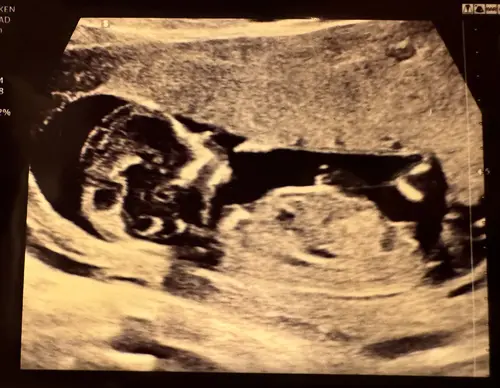

Wat denken jullie? 12w🩷🩵

Meisje, mooi rond hoofdje (skull theorie) en de nub ook gelijk aan de ruggengraat. 🩷🩷